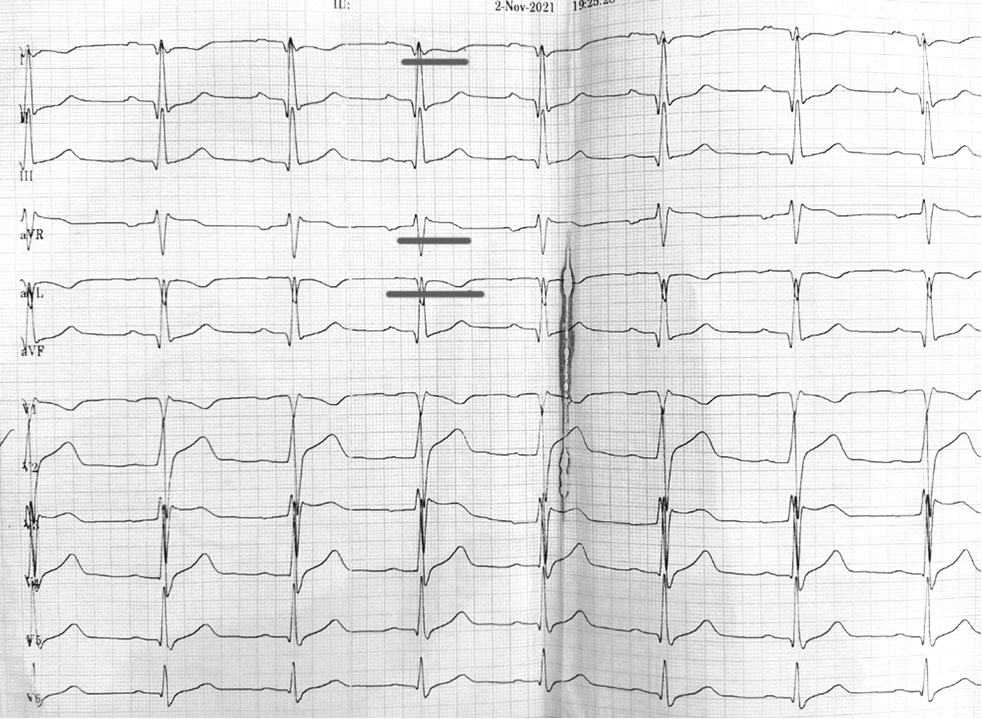

На электрокардиограмме (ЭКГ) на фоне нормосистолии с частотой сердечных сокращений 74 уд/мин выявлялась неполная блокада правой ножки пучка Гиса (ПНПГ), изменение процессов реполяризации в I и aVL отведениях, небольшая горизонтальная депрессия сегмента S–T с инверсией зубца T, на фоне синдрома ранней реполяризации желудочков (рис. 5).

Рис. 5. ЭКГ при поступлении в стационар. Указаны изменения процессов реполяризации в I и aVL отведениях, небольшая горизонтальная депрессия сегмента ST с инверсией зубца T

Fig. 5. Electrocardiogram at hospital admission. Changes in repolarization processes in the I and aVL leads, a small horizontal ST segment depression with T wave inversion are indicated